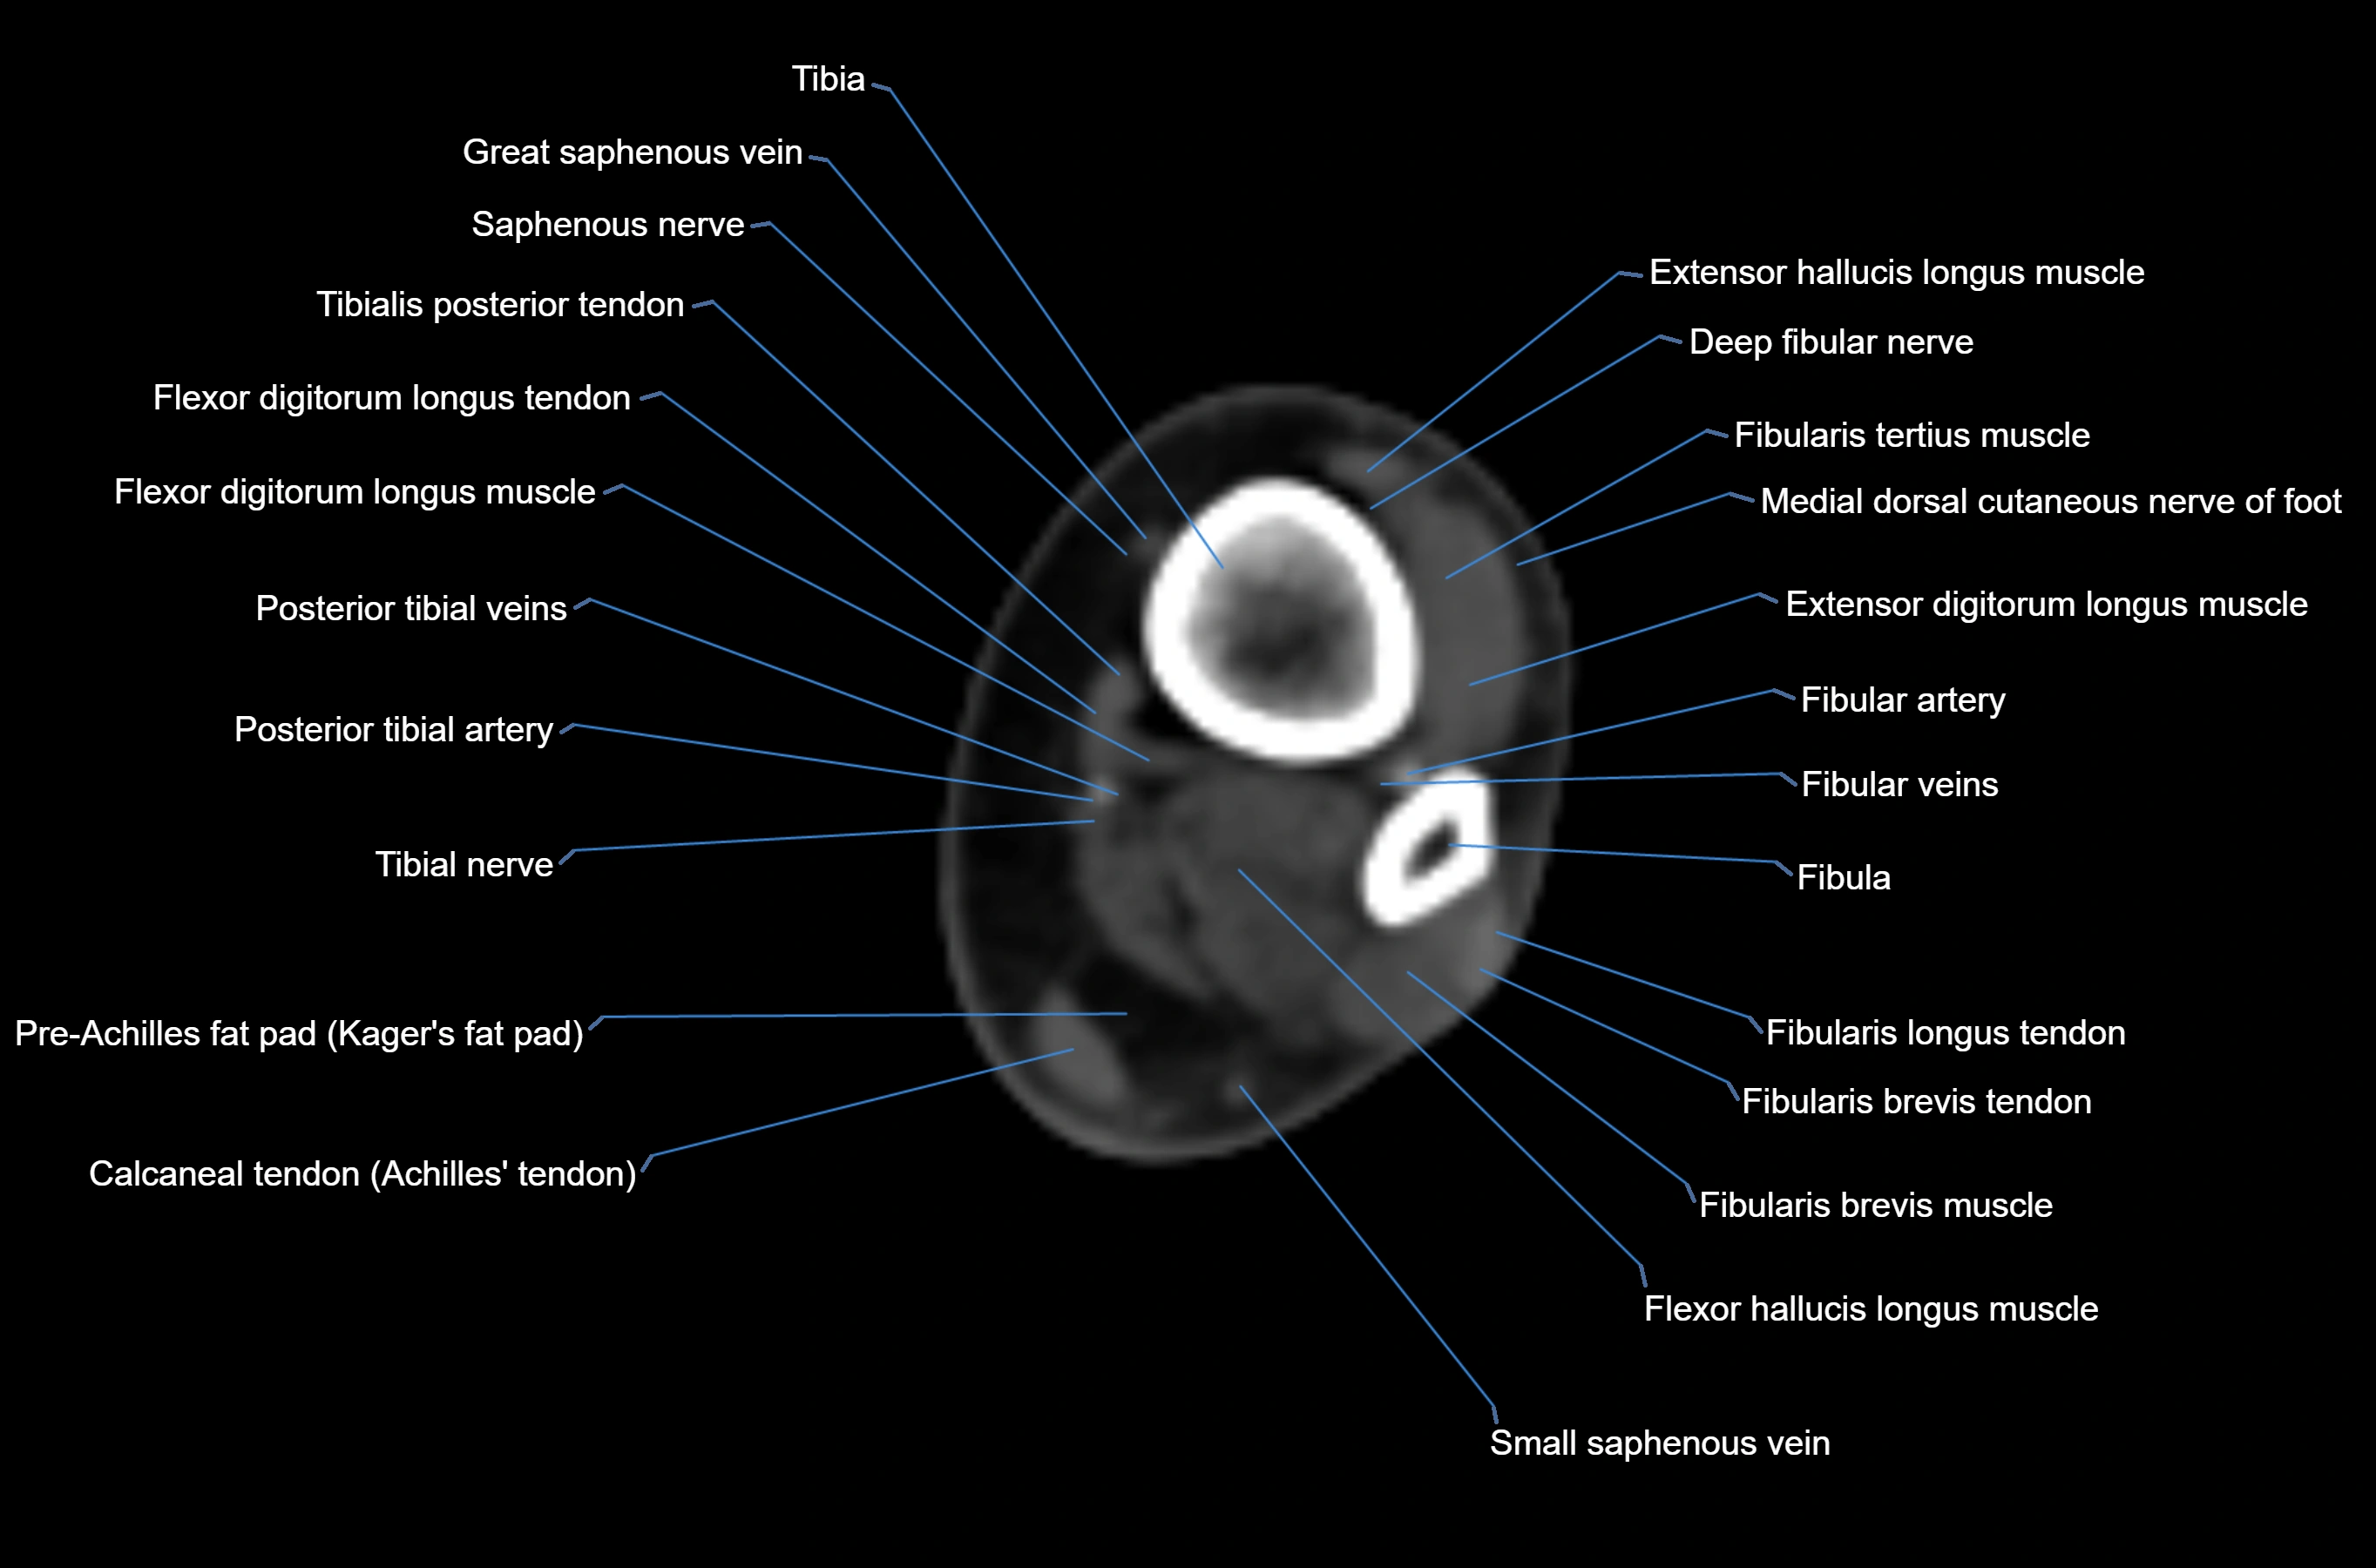

MRI image